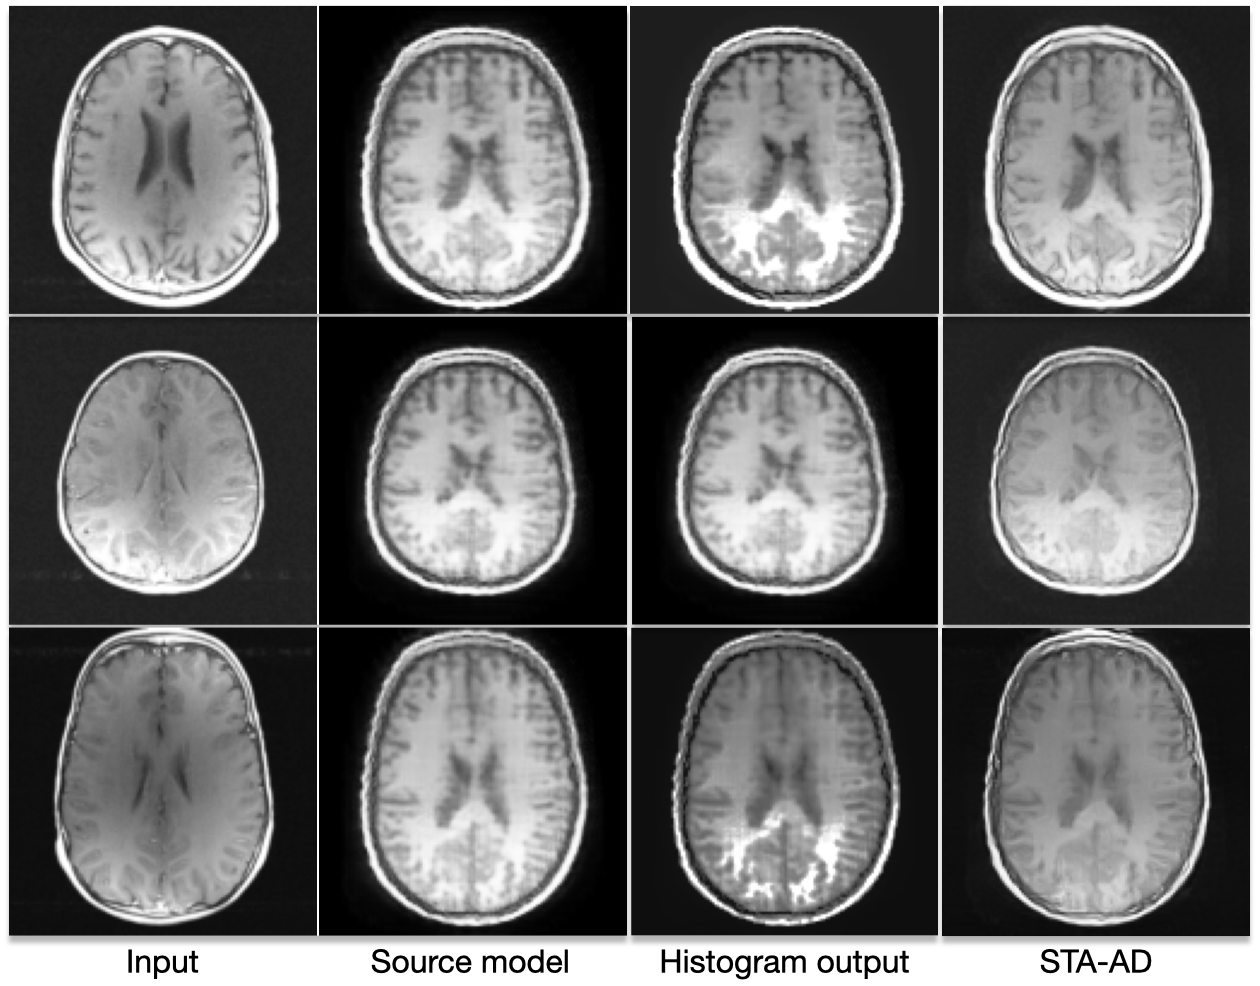

Refer to caption

Figure 5: Visual results of histogram matching and our method on the target dataset. These outputs are obtained by using the target input image and source model predictions as inputs. For histogram matching, the outputs result in visually incorrect results, introducing significant artifacts that degrade the final image quality. Whereas our method yields an adapted image that preserves image quality and thereby improves anomaly detection.